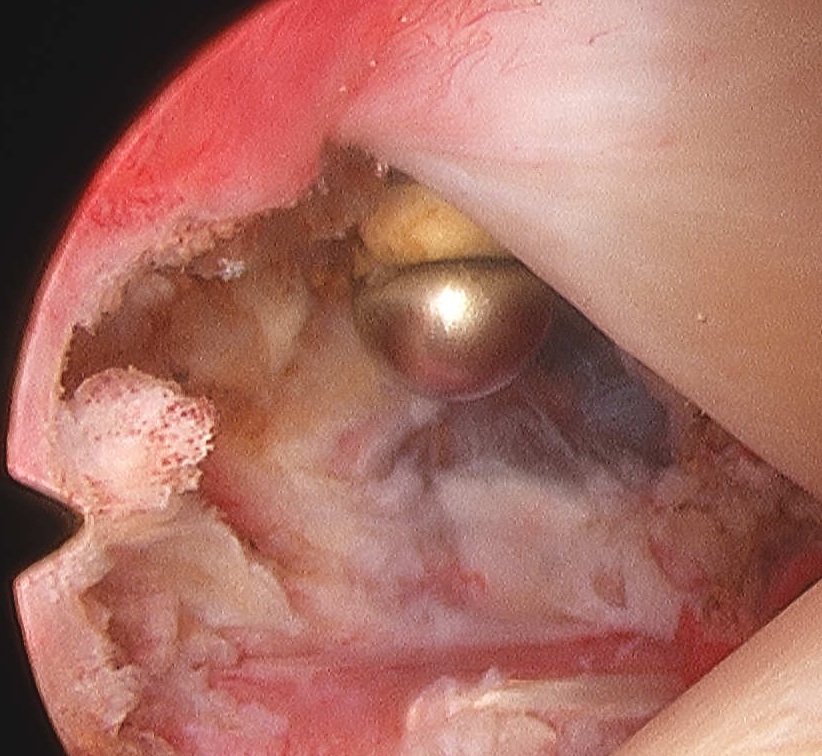

Arthroscopic capsular release

Technique

Release rotator interval - remove all tissue in between biceps and SSC

Mobilze subscapularis front and back from scar tissue

Release anterior IGHL from 3 to 5 o'clock, leaving labrum intact

Release posterior IGHL from 9 to 11 o'clock, leaving labrum intact

+/- release inferior capsule, beware injury to axillary nerve

Rotator interval release